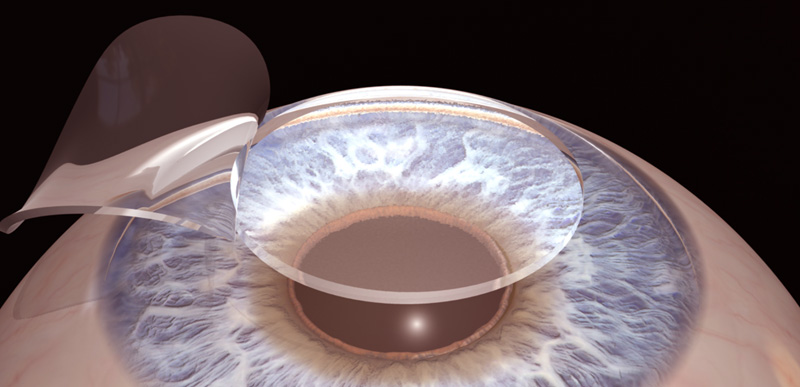

The word LASIK is an abbreviation obtained with the initials of Laser Assisted in-Situ Keratomileusis. LASIK method is the ultimately perfected form of techniques by using laser technology which were actually initiated in 1949s and called lamellar refractive surgery. Within this technique, the principal is removing the epithelium layer located at the frontmost of the corneal tissue, and the Bowman layer (a layer without the characteristic of self-perpetuation) with a device called microkeratom or femtosecond laser (flap). Afterwards, Excimer Laser performs the shaping process on the middle layers and when it is completed the removed flap is adhered on its original place. The flap is well-adhered due to the liquid pump in the cornea.

Lasik method is a two phased process comprising of flap shaping and reshaping of cornea with excimer laser. For flap formation, power-operated microkeratom which is a special blade or femtosecond laser is used. Different terms are used depending on modifications which result in incomprehensibilities: iLasik, sLasik, zLasik, FemtoLasik, etc. Consequently, the basic principle of the process is same for all. Also, Excimer lasers of different brands are available on the market.

Flap Formation with laser (Incision without blades)

The first stage of the lasik method is to form a flap of 90-120 microns on the corneal layer. Flap formation had been done with mechanical microkeratom blades for years.

However, flap is formed completely by Femtosecond laser without using any blades in femtolasik method. Femtosecond laser beams form a incision in accordance with the diameter, thickness, deepness and direction planned. Therefore, it is ensured that the flap incision is done securely in the thin cornea, small eyes and the eyes that have been previously operated.

Thus, the risk of incision complications is reduced such as free flap, buttonhole, incomplete flap that are seen with keratome. The thickness of flap may deviate +- 20 microns in keratomes as it is possible to obtain the required thickness and size of flap with femtosecond laser as well as the healing is quicker due to proper flap.